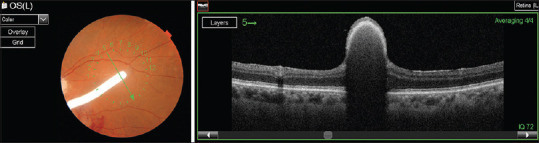

Foveal adhesion of a dexamethasone implant: Evaluation and follow-up via multimodal imaging.